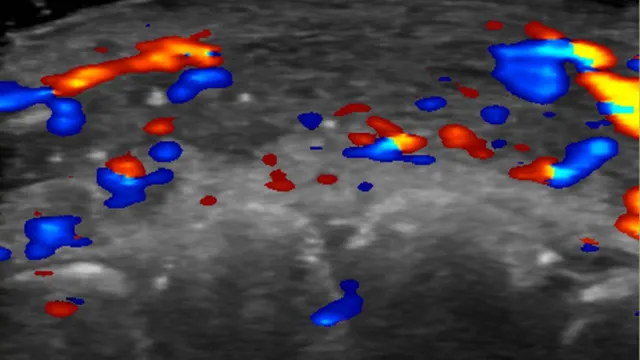

In just under half the cases, ultrasound scans showed absent blood flow to small blood vessels that connect superficial arteries to deep ones in the face.

And in a third of cases, blood flow was absent in major blood vessels.

Rosa Maria Silveira Sigrist, M.D., and RSNATo avoid complications in the first place, she advises clinics to use ultrasound to plan where to inject.